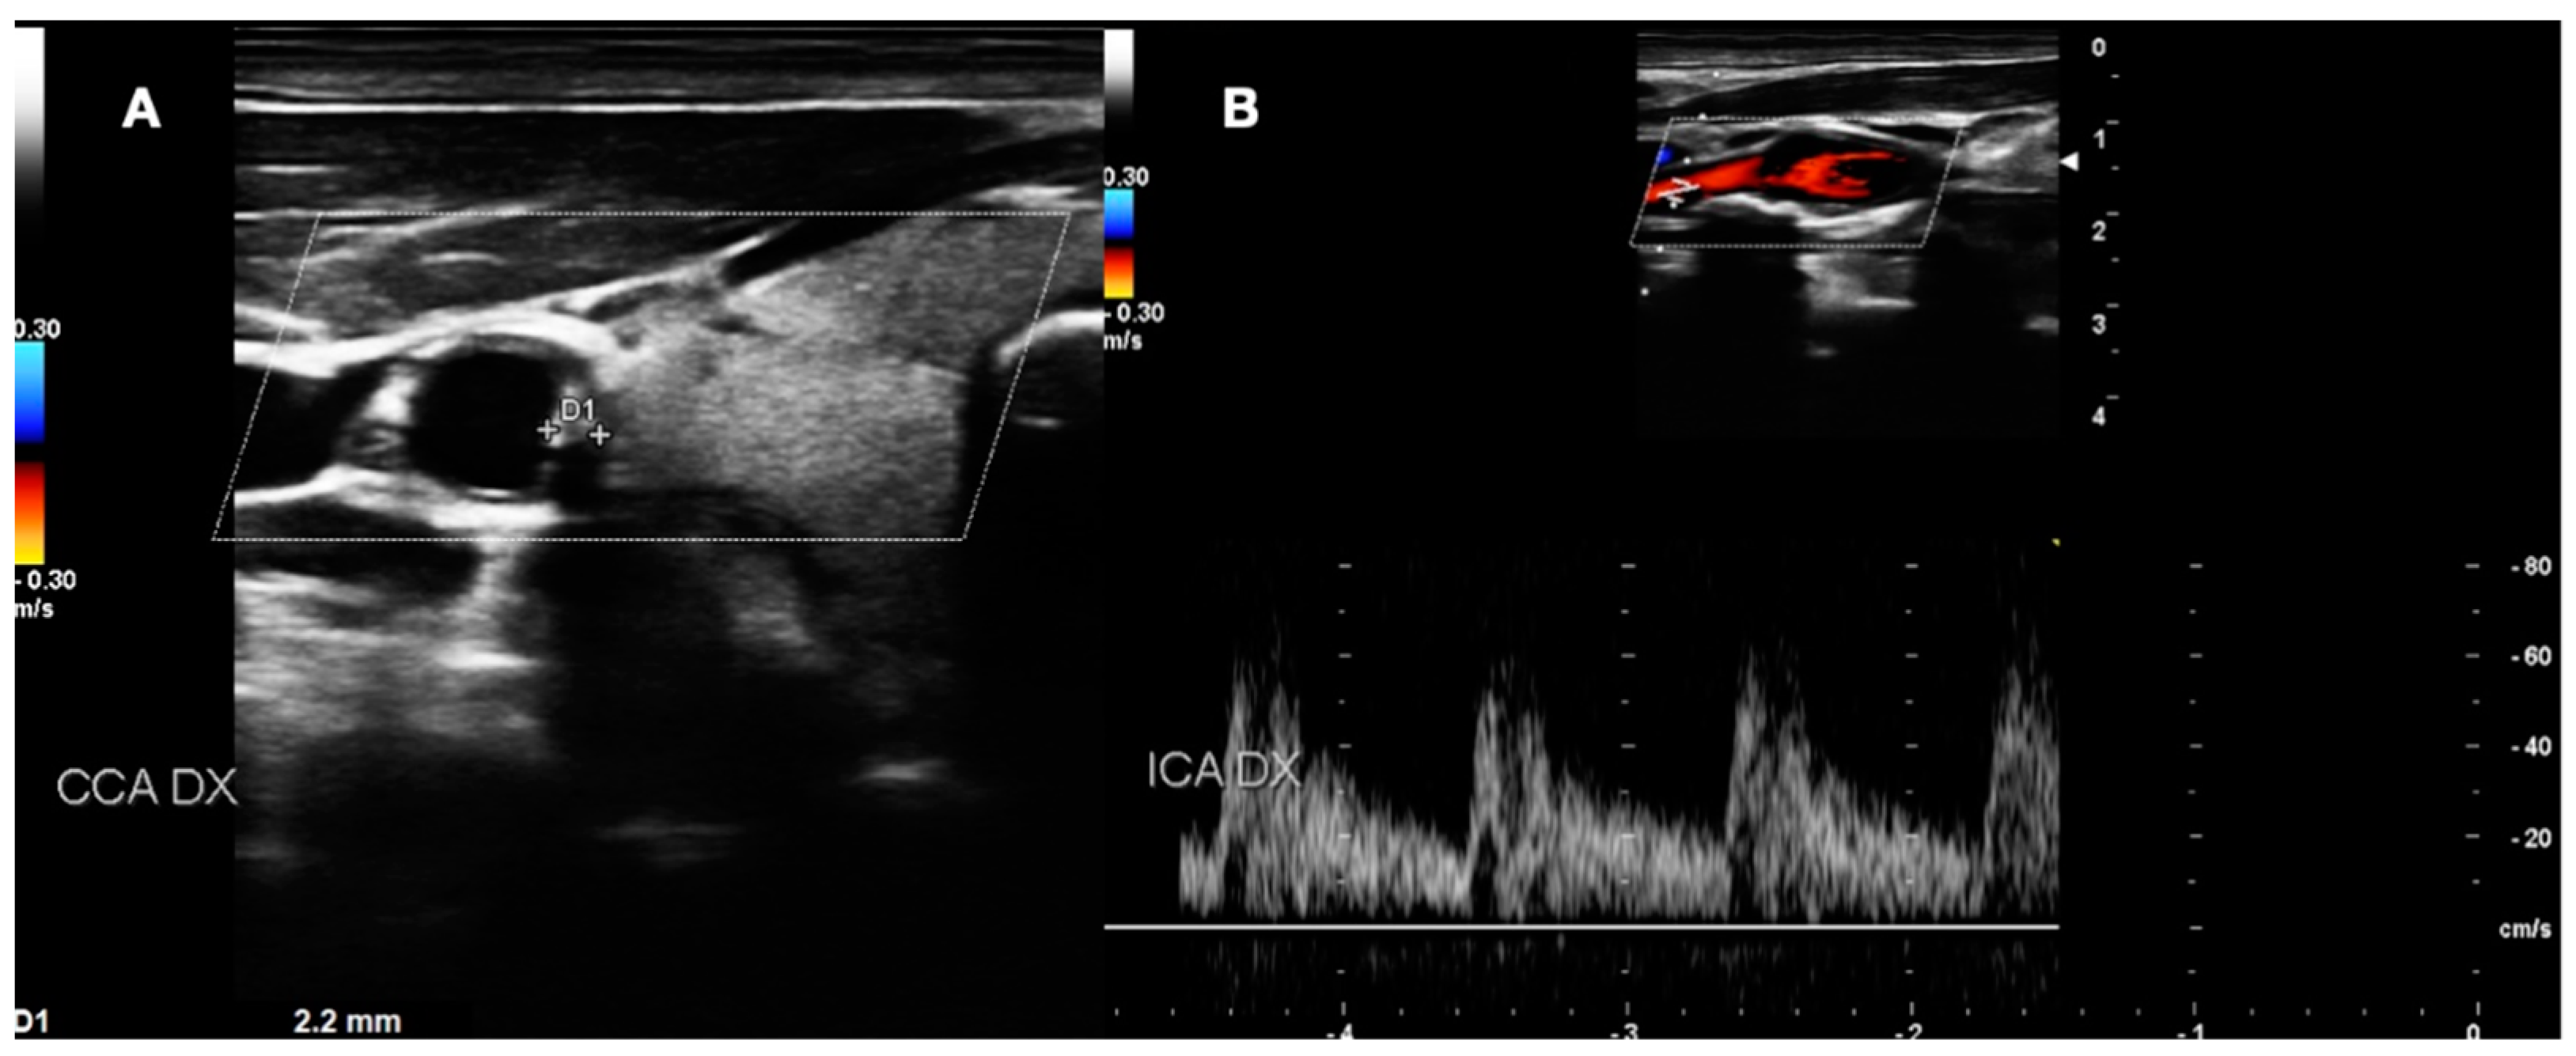

- BORDERLINE: Patients with IMT within the range of 1 mm to 1.5 mm. Here, considering the absence of true plaque but the presence of first modifications in the intima layer, our protocol provided a clinical evaluation with the risk factor identification (Figure 4).

Figure 4. DUS image showing plaque in CCA—BORDERLINE.